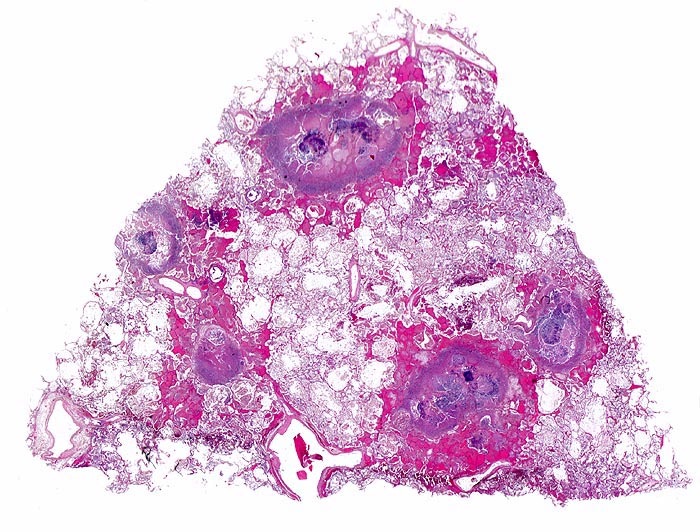

Morphologische Merkmale:

• Multiple Herde mit zentraler Nekrose und hämorrhagischem Randsaum.

• Pilzmyzelien, zerfallende neutrophile Granulozyten und Erythrozyten im Zentrum der Herde.

• Kräftig gefärbte Pilzhyphen mit 45° Verzweigungen.

• Hämorrhagischer Randsaum um die Nekrose: Hyperämische Alveolarwandkapillaren. Alveolen angefüllt mit Blut, Fibrin und Alveolarmakrophagen.